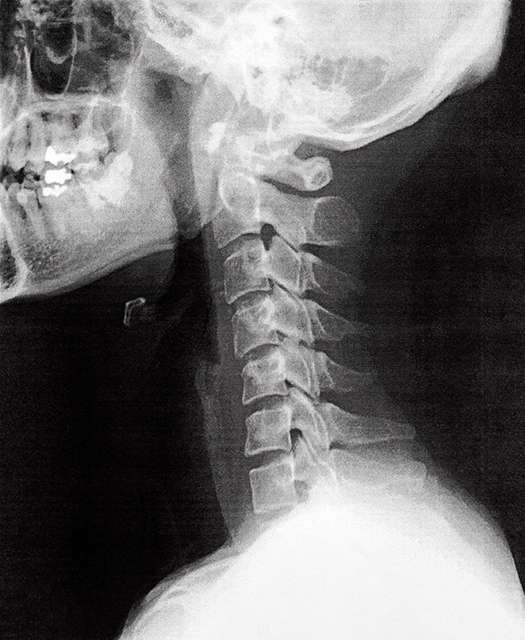

むちうちとは、主に追突事故など交通事故の衝撃で、首が鞭(むち)のようにしなり、首やその周辺にダメージを受けた状態の総称です。

事故の瞬間に、首が急激に前後に振られることで、筋肉や靭帯など軟部組織が損傷。

それによって、痛みや可動域の制限などの症状が、引き起こされると、言われています。

レントゲンやMRIとかで、骨とか神経を検査するんだね!

しかし、むちうち症状の多くは、筋肉や靭帯など、

骨以外の、軟部組織の損傷

であるため、レントゲンでは「異常なし」と判断されてしまうケースが非常に多いのが実情です。